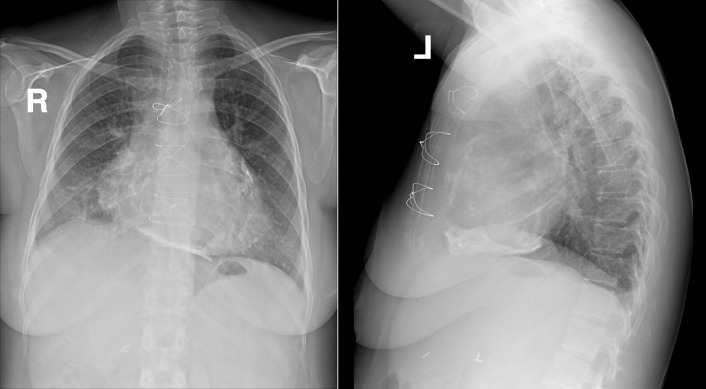

Pericardial Calcification

Pericardial calcification ( Figs. 27-1 to 27-4 ) is most prominent in the interventricular and atrioventricular grooves, and lateral to the right atrial and ventricular walls ( Graphic 27-1 ). When looking for pericardial calcification, it is necessary to scrutinize the lateral chest radiograph well, particularly the diaphragmatic surface. Pericardial calcification does not usually involve the left heart as much the right heart, and it does not often involve the apex (which, if calcified, is far more often due to prior infarction). Pericardial calcification should prompt serious consideration of the diagnosis of constrictive pericarditis, and clinicians should seek other radiographic and clinical features of constriction.